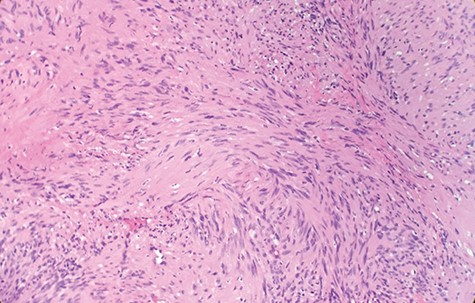

Macroscopically, the tumor appeared encapsulated, rubbery and pink-tan in color. Microscopic examination reveals that tumor composed of biphasic spindle hypercellular Antoni A areas and hypocellular Antoni B areas (Fig. 1). Higher magnification reveals that spindle tumor cells are narrow, elongate, wavy with tapered ends interspersed with collagen fibers (Fig. 2). Immunohistochemical staining revealed that most tumor cells reacted strongly for S-100 protein (Fig. 3). Combined with immunohistochemical profile, these histological features are diagnostic of benign schwannoma. Patient was discharged home on the same day as the operation. At the 1-month follow-up, he was symptom free, without any pain or sensory disturbances.

Higher magnification reveals spindle tumor cells are narrow, elongate, wavy with tapered ends interspersed with collagen fibers (×20).

Diagnostic criteria for schwannoma requires a biphasic cellular pattern, consisting of two distinct regions namely Antoni A and Antoni B. Antoni A is hypercellular with eosinophilic cytoplasm, whereas Antoni B is hypocellular and has loose tissue comprising clear, vacuolated cytoplasm due to lipid accumulation. In addition, nuclear palisading is a typical feature and when pronounced forms Verocay bodies [4].